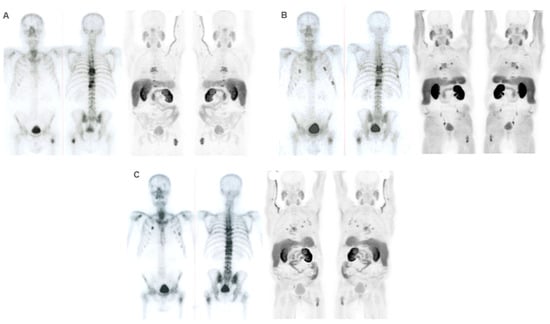

Regarding binary imaging response (progression vs. no progression), progression was more frequently observed in FCH PET/CT scans both at interim and end-treatment compared to BS. According to the progression pattern in interim FCH PET/CT, in most cases, progression was osseous, but in fifteen of them, soft tissue involvement was observed: three were exclusively nodal, seven were nodal and osseous, and five were visceral and osseous; 57% and 47% of patients progressed in interim and end-treatment FCH PET/CT, respectively. In end-treatment FCH PET/CT, the progression was eleven exclusively osseous, three nodal, one visceral, two osseous and nodal, and one osseous and visceral. The degree of agreement between interim BS and FCH PET/CT was weak (k: 0.349; p < 0.001), being higher in the case of binary response assessment (progression vs. no progression) (k = 0.447; p < 0.001). No agreement was observed between end-of-treatment studies (k = 0.157; p = 0.120 and k = 0.211; p = 0.075) in binary response. The distribution of results is shown in Table 4 and Table 5.

Performance status before 223Ra (p < 0.001), AP baseline levels (p < 0.001), and LDH (p = 0.033) were found to have a significant impact on OS (Figure 1), as well as other factors such as completion of treatment with 223Ra (p < 0.001). Regarding imaging variables, both the chi-square and the log-rank tests showed that derived FCH PET/CT variables had statistical significance. Thus, high tumor burden (p = 0.003), uptake of the most hypermetabolic lesion above the liver (p < 0.001), or STI in the FCH PET/CT study (p = 0.048) were associated with a lower median OS (Figure 2). Focusing on treatment response assessment, only interim studies (BS and FCH PET/CT) showed a significant association with OS, with data extracted from FCH PET/CT being slightly more robust compared to BS (p < 0.001 vs. p = 0.004, respectively) (Figure 3). The significant variables in the univariate analysis were included in the multivariate analysis for the OS and therapeutic failure end-points. In the former, the association of uptake of BM above the liver (p = 0.011), therapeutic failure (p = 0.001), or pathological baseline AP (p = 0.011) was highlighted as leading to lower OS. Table 8 details the results of the univariate Cox regression, and Table 9, Table 10 and Table 11 show the results of the log-rank test regarding OS.

Regarding BS, BSI has been defined as very useful for both evaluating treatment response and predicting the prognosis of treated patients [16]. In the present work, BM progression was established on BS using NPCP criteria, although without the needed confirmation on a second scan according to the 2 × 2 rule. In addition, for a more reproducible comparison, we used the same criteria for FCH PET/CT. Only interim BS and FCH PET/CT showed significant association with OS with the strongest relation of binary response (progression vs. no progression) for interim FCH PET/CT (Table 10).

Regarding the response to 223Ra treatment, our results showed a significant association between non-progression in both BS and FCH PET/CT in interim studies and greater OS, being more notable with FCH PET/CT (Table 11 and Figure 3).

Figure 3. Kaplan–Meier OS curves of binary response in interim FCH PET/CT scans (left panel) and BS (right panel).

Cancers 16 02695 g003